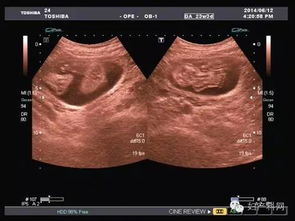

超聲波檢查,通過(guò)超聲波檢查出胎寶寶的體重、位置、大小。胎盤(pán)位置、羊水數量、呼吸運動(dòng)等情況,以便判斷是進(jìn)行自然分娩還是剖腹產(chǎn)

特別是對于月經(jīng)不準或者記不清楚最后一次月經(jīng)的孕媽媽來(lái)說(shuō),在懷孕早期可以利用超聲波檢查預見(jiàn)預產(chǎn)期。還可以檢查胎兒是否缺氧,或者孕婦是否是宮外孕。但是,超聲波最主要的還是堅持寶寶在腹中的生長(cháng)情況。

現代社會(huì ),雖然科技在不斷發(fā)展,但是環(huán)境也在受到更嚴重的污染,這就導致了許多畸形胎兒的生長(cháng),而超聲波檢查就能告訴你胎兒生長(cháng)是不是正常,是否有什么缺陷,有特別的情況的話(huà),醫生通過(guò)超聲波檢查可以告訴你,比如,有些遺傳病可以在寶寶出生之前檢查出來(lái),比如營(yíng)養性肌肉發(fā)育不良,如果是男孩的話(huà)很容易造成遺傳,這樣的話(huà)醫生會(huì )通過(guò)檢查結果告訴你最好不要孩子。

一般來(lái)說(shuō),在第18周-20周進(jìn)行第一次超聲波檢查。它能大致診斷出胎兒是否畸形,觀(guān)察胎兒的活動(dòng)狀態(tài)。

在懷孕第34周第二次超聲波檢查的目的是監測羊水量、胎盤(pán)位置、胎盤(pán)成熟度及胎兒有無(wú)畸形,了解胎兒發(fā)育與孕周是否相符。 最后是在第37周以后,超聲檢查主要目的是確定生產(chǎn)方式,為了監測羊水量、胎盤(pán)成熟度,必要時(shí)需要每周一次B超。